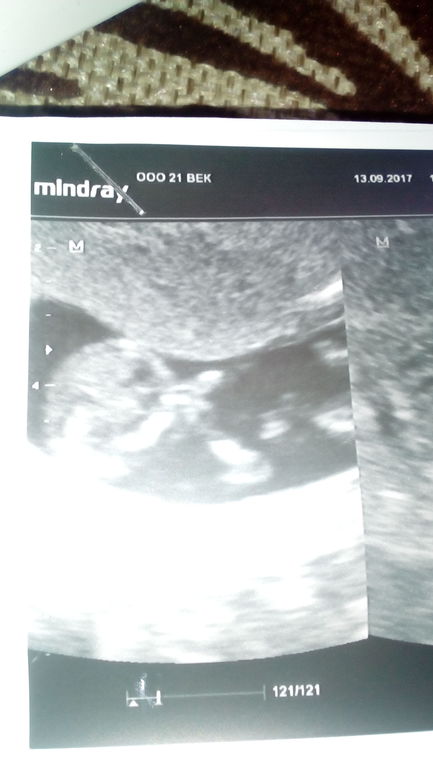

вот наши ручки на лице